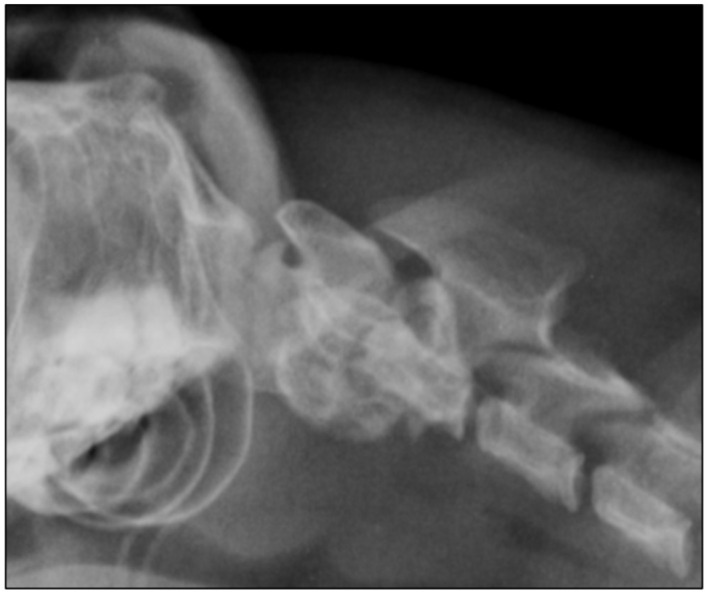

病例总结:本病例报告中描述的猫表现为进行性非活动性四肢全瘫。它被诊断为枕骨寰枢畸形(OAAM),导致严重的压缩性脊髓病。这种情况是由枕髁变平和椎体轴变短引起的。此外,在CT上观察到寰枢关节发育不良。这只猫接受了手术治疗,使用了一个板,这是在畸形的三维模型的帮助下定制的。手术后三周,这只猫能够在没有帮助的情况下行走;术后5年,猫的神经系统检查正常。相关性和新信息:使用三维技术的手术计划在复杂的OAAM病例中是有用的。这是第一个记录在案的猫科动物使用这种技术治疗这种疾病的病例。

Case summary: The cat described in this case report presented with progressive non-ambulatory tetraparesis. It was diagnosed with an occipitoatlantoaxial malformation (OAAM), which resulted in severe compressive myelopathy. This condition was caused by a flattening of the occipital condyles and shortening of the vertebral body of the axis. In addition, there was dysplasia in the atlantoaxial joint, which was observed on CT. The cat was treated surgically using a plate, which was custom-made with the help of a three-dimensional model of the malformation. Three weeks after surgery, the cat was able to walk without assistance; 5 years after surgery, the cat showed a normal neurological examination.